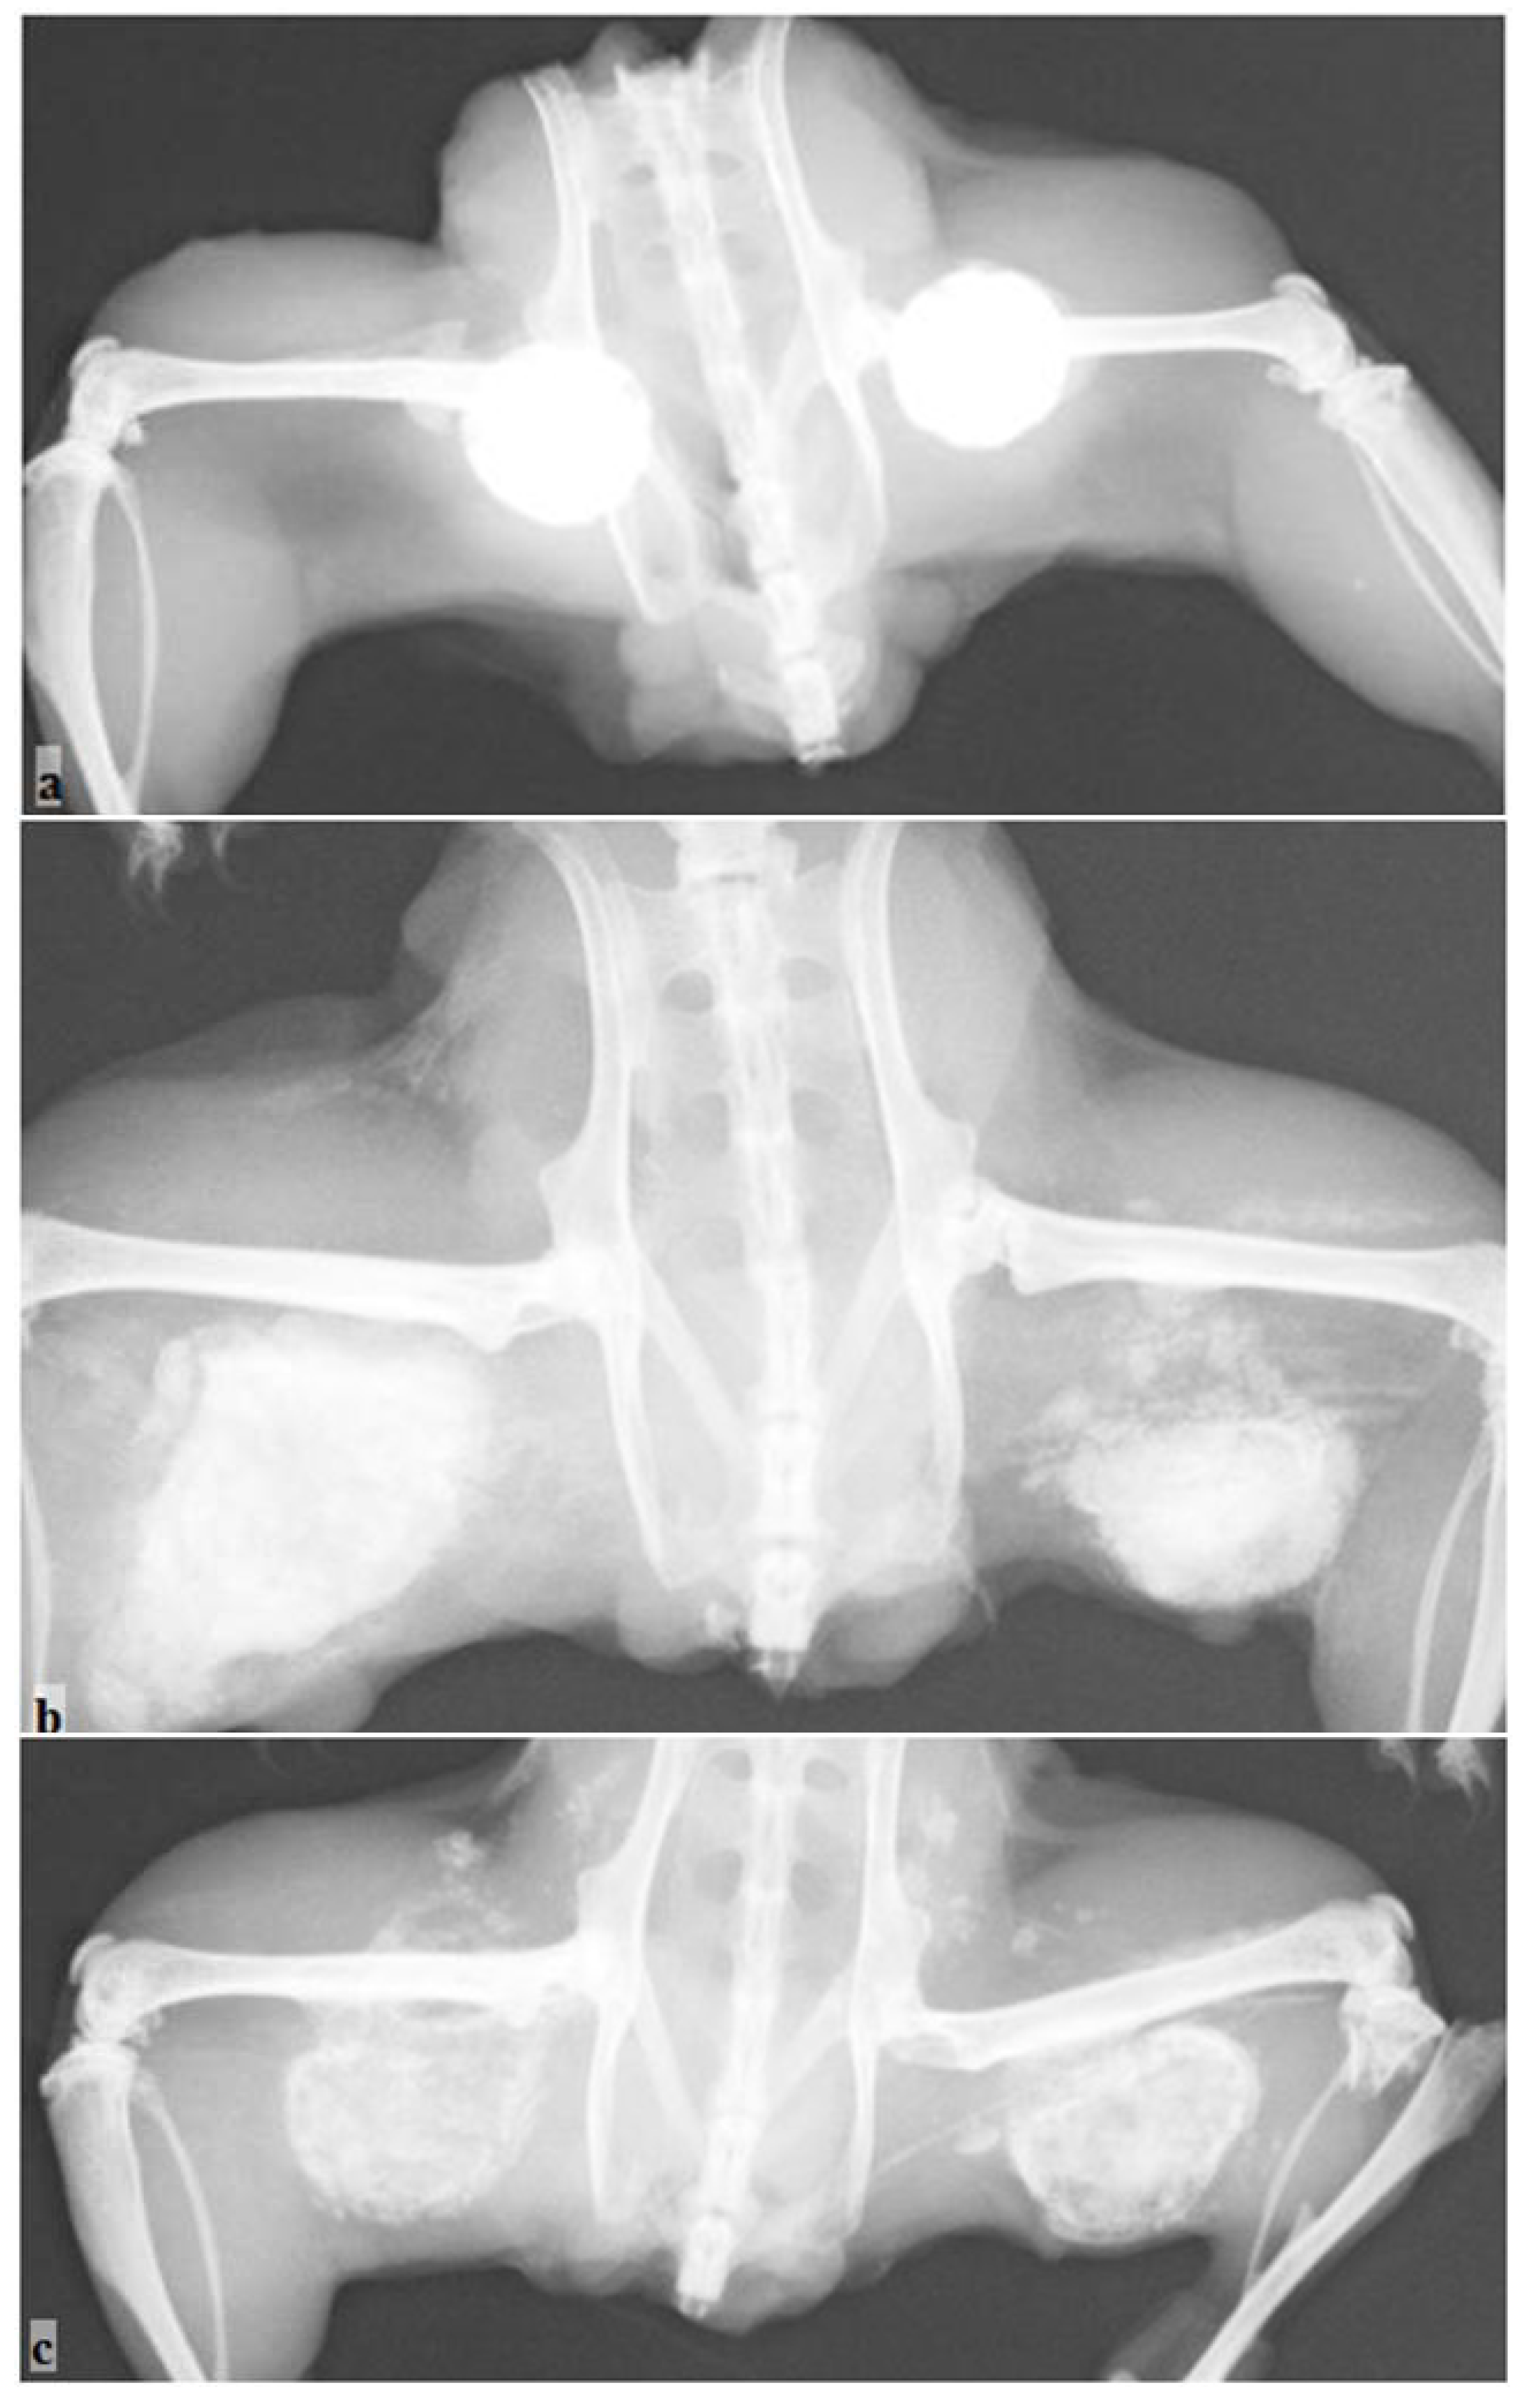

The protein profile and the bioactivity of the dry bone protein extract were evaluated using the SDS-page [22] and the mouse muscle pouch model study (Figure 1).

Figure 1. The histological examination shows the bioactivity and the new bone formation for a 3 mg dose of reindeer bone protein extract in a gelatin capsule in the mouse pouch model. B = bone. (Original magnification 10×).

The reindeer bone protein extract has high bone formation activity, as seen in the bioactivity and previous tests (Figure 1); however, in a real bone healing situation, the extract cannot work without a scaffold system. Limitations of the carrier selection are set by the characteristics of the reindeer bone protein extract. The primary limitation is that the extract is not water-soluble. Thus, there are at least three different possibilities for implant preparation. The first is that the formulated bone extract suspension can be impregnated into a porous matrix (Figure 2a). The second method is to mold the extract and carrier together to form putty or compress them into the discs (Figure 2b), and in the third method, the carrier discs or granules are surface coated with the bone extract. Pure collagen has been tested as a carrier in some of our previous studies [18,19,21]. Lyophilized extract was mixed into water and then pipetted onto the collagen sponge; alternatively, the collagen sponge was soaked in water and then, with the extract, was bundled up to form an implant. The results of this method showed good bone formation in the pouch mice model and in the segmental defect model; however, it seems that collagen does not support the functionality of the bone forming proteins in the required time [24]. Therefore, an inorganic alternative would provide a better frame for the support of the bone healing effect of the extract. Previously, we have tested combinations of TCP, HAP and coral together with the extract and collagen sponge in the mouse model [17]. Furthermore, bioglass was found to be an acceptable carrier alternative as tested in the rat defect model [20].